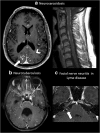

Purpose: Miliary enhancement refers to the presence of multiple small, monomorphic, enhancing foci on T1-weighted post-contrast MRI images. In the absence of a clear clinical presentation, a broad differential diagnosis may result in invasive procedures and possibly brain biopsy for diagnostic purposes.

Methods: An extensive review of the literature is provided for diseases that may present with miliary enhancement on T1-weighted brain MR images. Additional disease-specific findings, both clinical and radiological, are summarized and categorized by the presence or absence of perivascular space involvement.

Results: Miliary pattern of enhancement may be due to a variety of underlying causes, including inflammatory, infectious, nutritional or neoplastic processes. The recognition of disease spread along the perivascular spaces in addition to the detection or exclusion of disease-specific features on MRI images, such as leptomeningeal enhancement, presence of haemorrhagic lesions, spinal cord involvement and specific localisation or systemic involvement, allows to narrow the potential differential diagnoses.

Conclusion: A systematic approach to disease-specific findings from both clinical and radiological perspectives might facilitate diagnostic work-up, and recognition of disease spread along the perivascular spaces may help narrowing down differential diagnoses and may help to minimize the use of invasive diagnostic procedures.